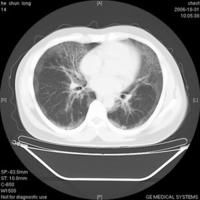

肺泡蛋白質(zhì)沉積癥(pulmonary alveolar proteinosis,簡稱PAP),又稱Rosen-Castle-man-Liebow綜合征。以肺泡和細支氣管腔內(nèi)充滿PAS染色陽性,來自肺的富磷脂蛋白質(zhì)物質(zhì)為其特征。好發(fā)于青中年,男性發(fā)病約3倍于女性。病因未明,可能與免疫功能障礙(如胸腺萎縮、免疫缺損、淋巴細胞減少等)有關。粉塵尤以接觸矽塵的動物可引起PAP,故認為可能是對某些刺激物的非特異反應,導致肺泡巨噬細胞分解,產(chǎn)生PAS陽性蛋白質(zhì)。